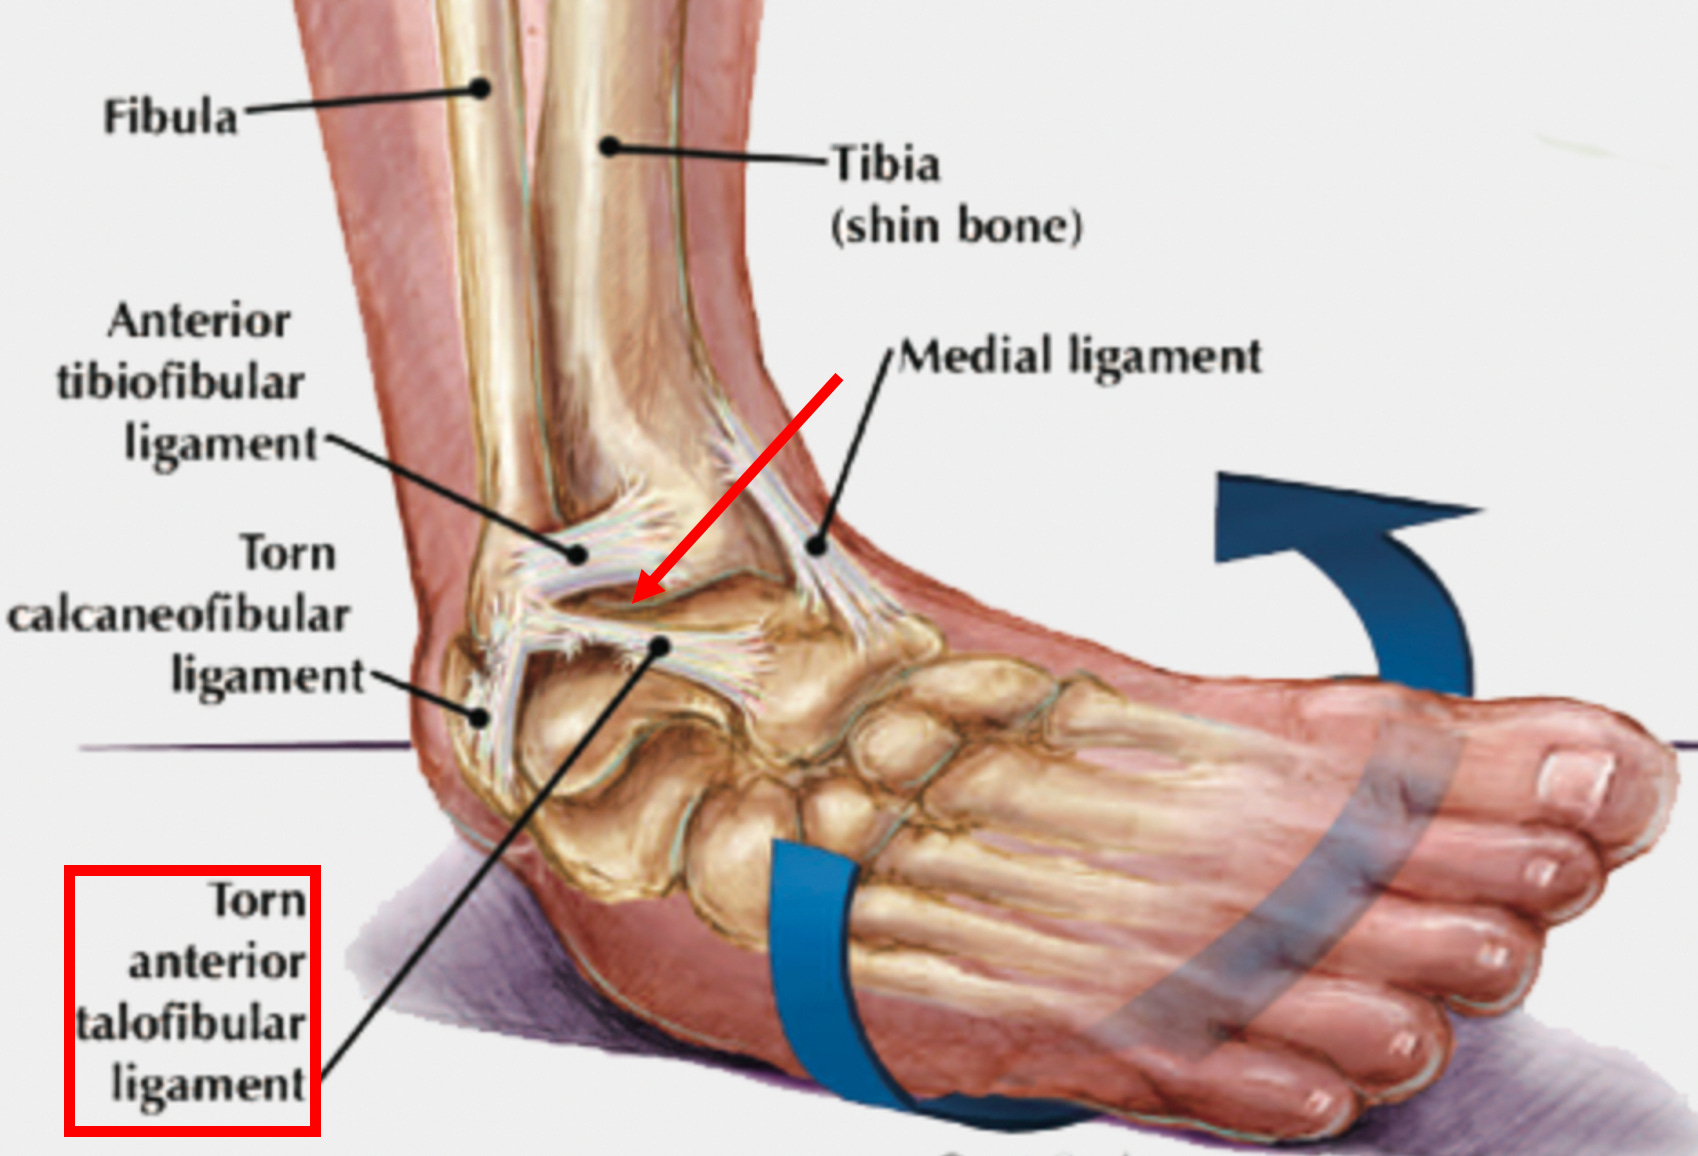

Ligamentous weakness is frequently caused by a chronic injury to a ligament (or an injury which did not properly heal). For example, when the ankle is injured from a sprain, the ligament that keeps the ankle from turning inwards gets damaged, predisposing us to an unstable ankle and future ankle injuries until the ligament is repaired and strengthened.

Pharmaceutical Injuries

In addition to physical injuries, biochemical injuries can also occur. This is best known to occur following the use of anti-inflammatory medications. For example, NSAIDS like Ibuprofen (which are typically the go to for “treating” sports injuries) in addition to reducing the discomfort of an ankle injury also weaken the ligaments (as by suppressing the inflammatory process it also suppresses the healing process).

This results in sprains that are treated with NSAIDs often being predisposed to future injuries (since the stability given to the joint by those ligaments is partially lost until something like a regenerative therapy is given to repair that ligament)—which in the case of ankle sprains is something I and colleagues frequently see in our patients.